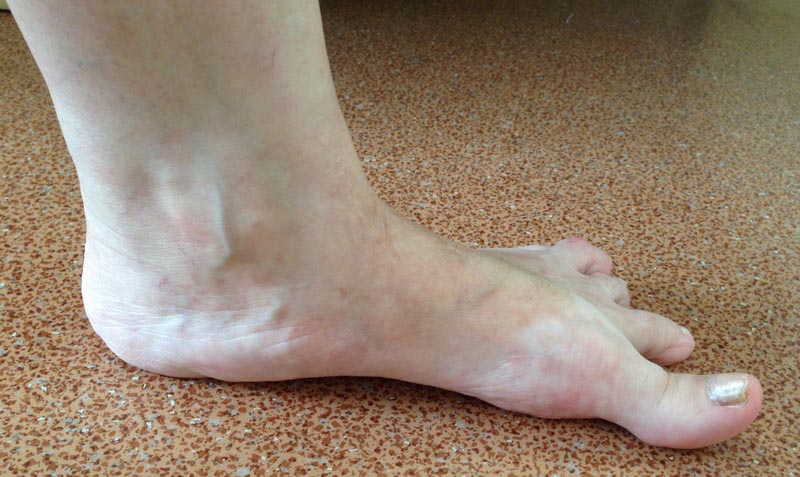

Пциентка Н, 58 лет. Больна с 2005г. Лечилась консервативно. Со слов,

тогда было сильное искривление 1,2,3,4 пальцев в латеральную сторону.

В 2012г. операция: коррекция деформаций 1,2,3, 4 пальцев.Рецидив.

В 2013г. коррекция деформации 2,3,4 пальцев. С ноября

2014г. рецидив деформации 1,2,3,4 пальцев.

Возможные варианты коррекции?